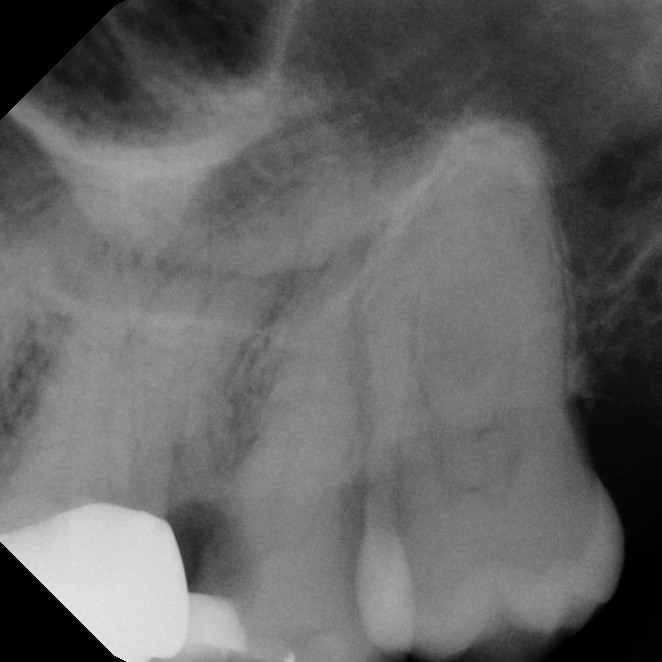

Sometimes, a tooth that has already undergone root canal therapy may not heal as expected or may develop new problems months or even years later. In these cases, endodontic retreatment offers a second chance to save the tooth. During this procedure, the existing filling materials are carefully removed from the canals, the inside of the tooth is cleaned again, and any hidden or untreated areas are addressed before the canals are sealed once more. This process allows your dentist to correct any issues and give the tooth the best possible chance for long-term success.

Thanks to modern tools and techniques, retreatment is a precise and effective procedure that can often be completed comfortably under local anesthesia. Many patients are surprised to learn that retreatment is no more uncomfortable than the original root canal. By choosing retreatment instead of extraction, you preserve your natural tooth, maintain your smile's appearance, and avoid the more complex and costly process of replacing a missing tooth.